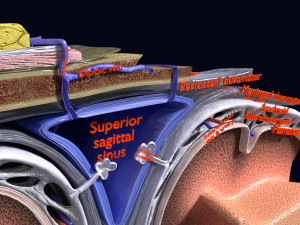

A blend model of brain along with its covering layers (meninges), skull bone and scalp labelled in detail and anatomically precise. The parts depicted are white, gray, pia, arachnoid, dura, bone, skin, fat, aponeurosis, periosteum, falx cerebri and more.

The material is high resolution image textures and normal maps based on non overlapping UVs. The texture and normal maps are packed with the blend file itself.